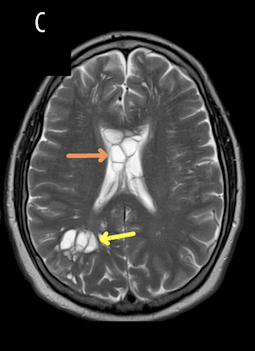

Zum Zeitpunkt der Erstvorstellung im Krankenhaus zeigten die Vitalwerte des Patienten keine Auffälligkeiten – so auch die neurologische Untersuchung. Aufgrund der besorgniserregenden und anhaltenden Veränderung der Migräneanfälle des Patienten wurde zunächst eine CT-Untersuchung durchgeführt und im Anschluss ein MRT des Gehirns. Die Bildgebung ergab folgende Befunde:1

Bildabschnitt C: Im Corpus callosum (oranger Pfeil) und im Okzipitallappen (gelber Pfeil) konnten zystische Läsionen im MRT nachgewiesen werden.1

Die Bildgebung ergab die Verdachtsdiagnose angeborene neurogliale Zysten

Im CT und im MRT konnten zahlreiche zystische Herde beidseitig im tiefen, kortikalen und periventrikulären Parenchym der weißen Substanz aufgezeigt werden. Diese waren diffus über jede Hemisphäre verteilt gewesen. Es gab keine Hinweise auf einen Masseneffekt oder einen Hydrocephalus, sodass ein Hirntumor als Ursache ausgeschlossen wurde. Die im CT und MRT nachgewiesenen Veränderungen wurden zunächst für angeborene neurogliale Zysten gehalten. Der Patient wurde umgehend zur rechtzeitigen neurochirurgischen Beratung in die Neurochirurgie überwiesen.1